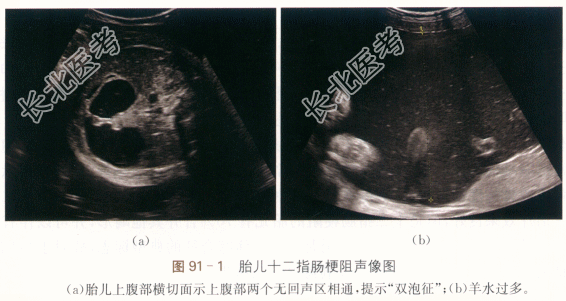

- 简答题1、若诊断为胎儿十二指肠梗阻,其声像图表现是什么?